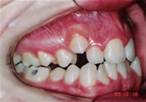

Paciente com maxila ( maxilar superior ) atrésico, respirador bucal e com espaçamentos entre os dentes. Se não tratado, terá sérios transtornos para os dentes, para aparência facial e para saúde como um todo.